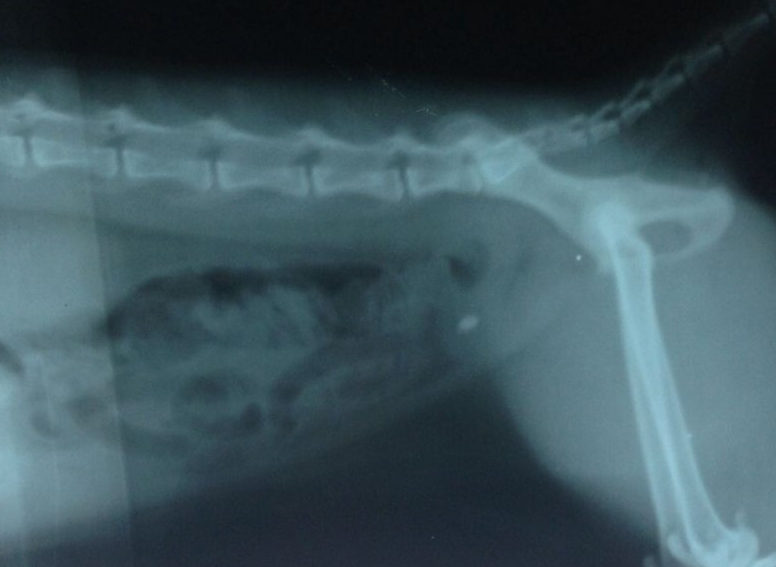

品种:加菲猫 名字:菲菲 年龄:三岁 性别:雄性

病史:一年前被现在的主人送人,送人半年后出现尿血,主人带到一个动物医院检查,当时未拍摄X光片 及B超检查,诊断为膀胱炎,打几天针有好转,但扔尿血,主人后来没有再带菲菲去医院继续治疗,只是在家饲养,菲菲在家饲养时常出现尿血、尿频、饮食饮水正常。

菲菲因为到处乱排尿,前几天收养人把菲菲还给了原来的主人,好心的主人发现此猫尿血赶紧带到我院来检查,根据菲菲的临床症状我们给它做了B超、X光、血常规检查、生化检查。